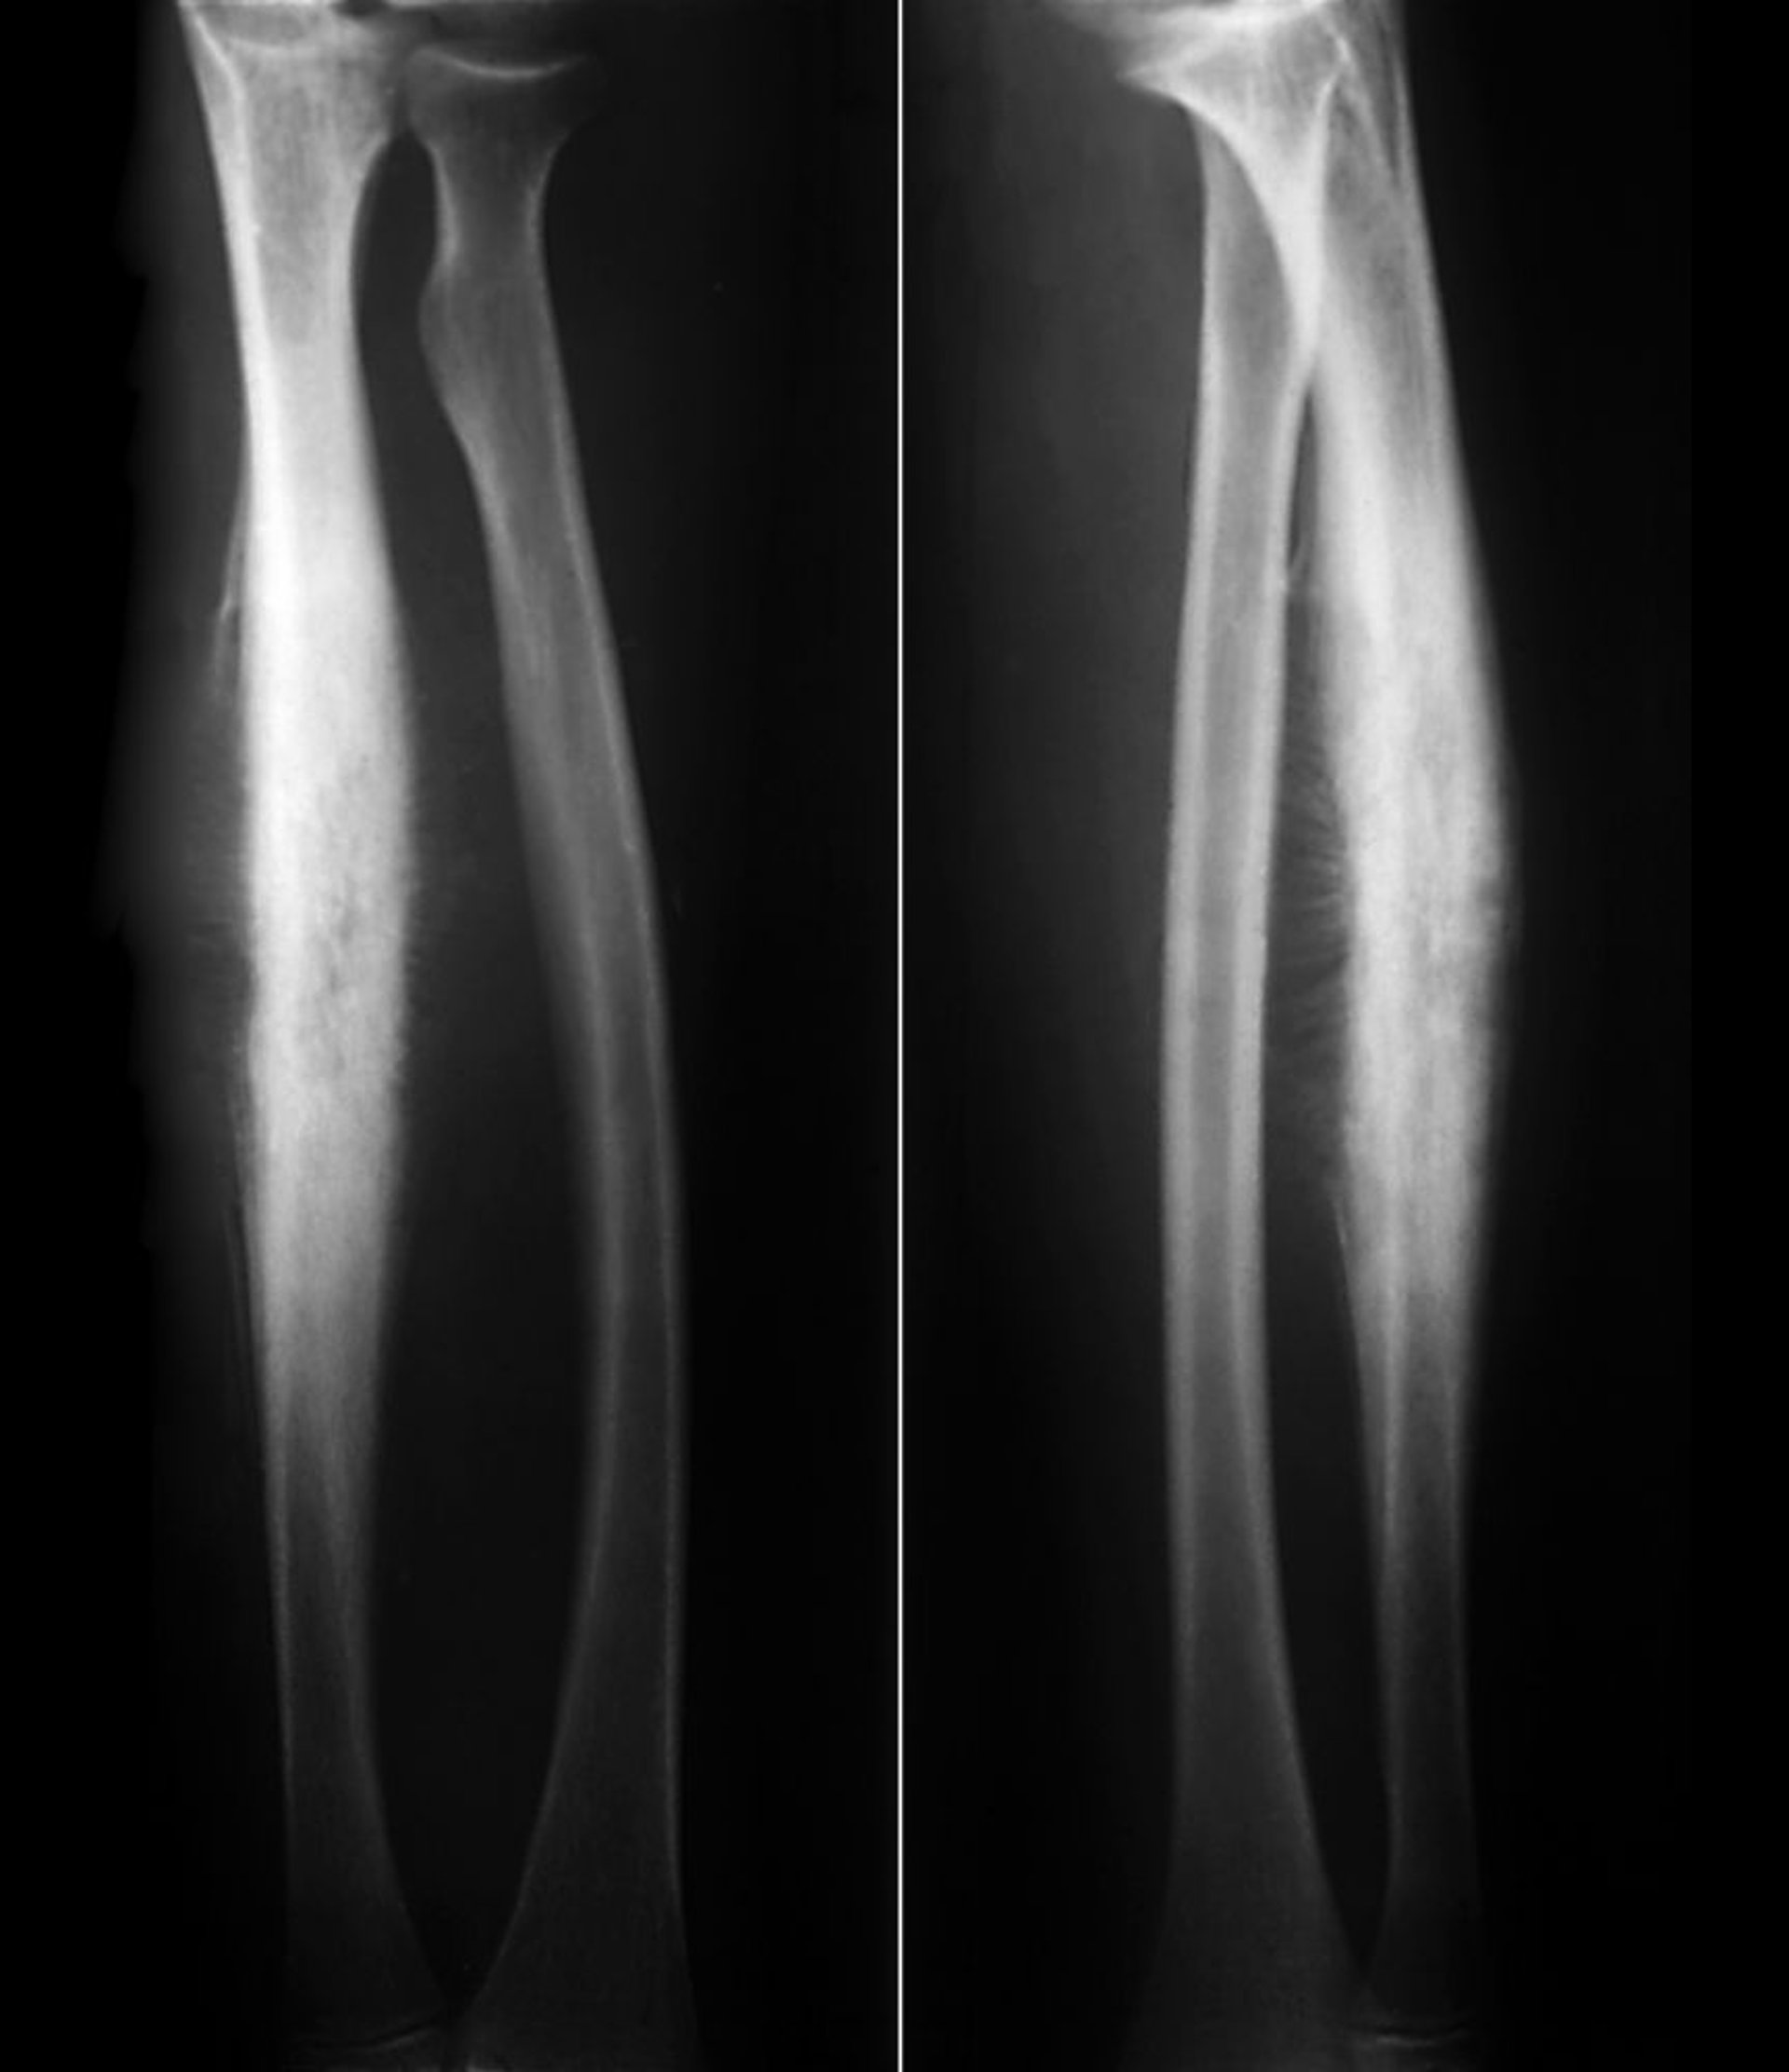

Sarcoma de Ewing del radio

Este sarcoma de Ewing de la diáfisis radial muestra una formación subperióstica de hueso nuevo reactivo en una reacción perióstica de "rayos solares" clásica junto con la destrucción lítica del hueso cortical.

ZEPHYR/SCIENCE PHOTO LIBRARY